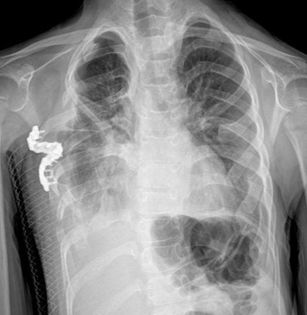

Lateral Thoracic Expansion is applied for the treatment of thoracic dystrophies (the most common among them is jeune syndrome) and other small rib cage deformities (for example, when rib anomaly accompanies another component of Poland's Syndrome, other than the absence of classical chest muscle, the rib cage may remain small). With a vertical incision from the side at the armpit level, the rib cage is expanded from the sides by reaching from the 4th rib to the 9th rib and making a connection between the ribs in a different way.

The purpose of this surgery is to widen the thoracic cage, making room for the patient's heart and lungs to grow, and thereby enabling the patient to continue his or her life. By applying the same operation to the opposite side within 6 months or 1 year, asymmetry is prevented and the lung on the opposite side can find a place to expand.

In this surgery, since we do not leave the expansion to screws and plates, and we apply it by combining bones in different formations, bone formation can continue over the years as the patient grows, and the thorax can expand as well, and strength is ensured by refilling that area with the bone tissues that the patient will create in that area. Thus, various complications do not occur with the dislocation of foreign objects such as screws and plates.